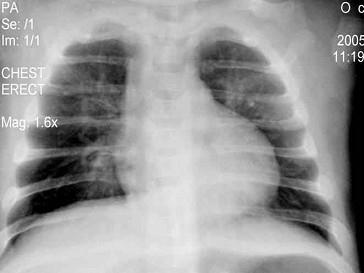

问题 6个月婴儿,持续高热810天,精神萎靡,时有烦躁不安,频繁咳嗽,喘憋。左下肺叩诊稍浊,呼吸音降低,闻及小水泡音,血白细胞8×10/L。胸部X线片示两肺纹理增多,可见大片状阴影,伴有肺气肿,见图。最可能的诊断是 ( )

选项 A、支原体肺炎 B、急性毛细支气管炎 C、腺病毒性肺炎 D、金黄色葡萄球菌肺炎 E、支气管肺炎合并中毒性脑病

答案 C